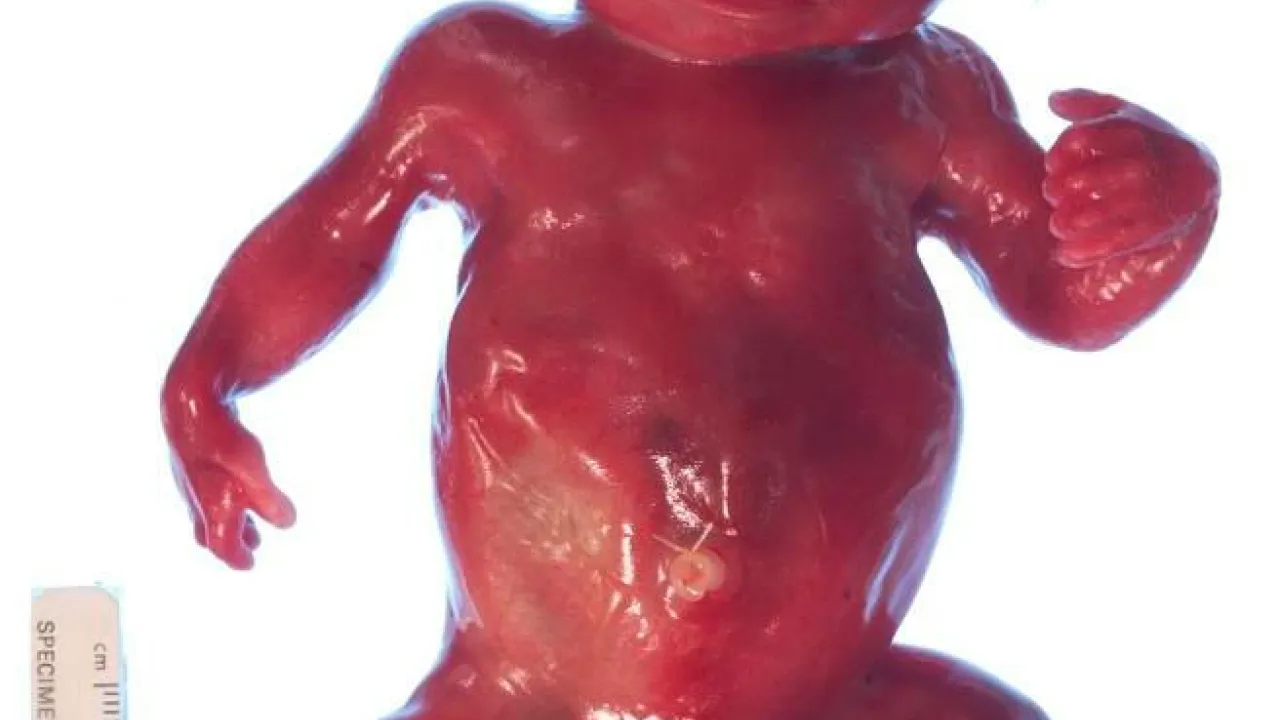

Skeleton and body morphology, Twin reversed arterial profusion sequence